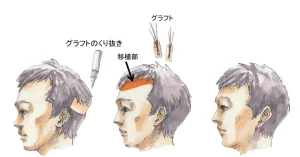

植毛手術において、FUE法(follicular unit excision)(後頭部や側頭部などの採取部から1つずつ特殊な器具を用いて毛包単位で採取していく方法)でもクリニックにより方法や工程が全く異なります。 施術工 […]

こんにちは、植毛医の内田直宏です。 移植床作成は植毛手術において採取作業と同等に最も大切な作業の1つです。 そもそも「移植床」や「ドナー」、「レシピエント」など、よく触れる言葉かと思いますが、それらが具体的に何を指してい […]